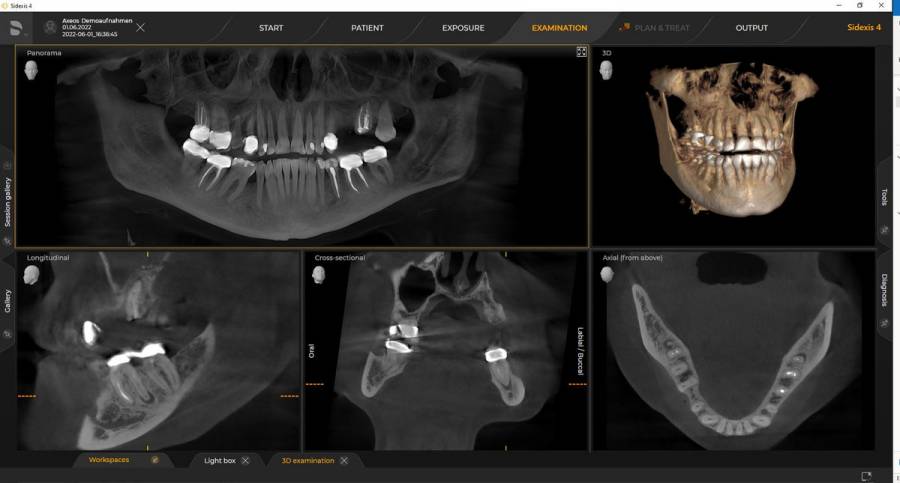

Rendelőnkben lehetőség van fogászati kisröntgen, panoráma röntgen, teleröntgen, CBCT felvétel készítésére. Az elkészített felvételeket digitálisan tároljuk rendelőnkben és szükség esetén átadjuk pácienseinknek is. A CBCT képalkotás olyan nagy mennyiségű információt és hajszálpontos részleteket is feltár, amiket semmilyen 2D-s intraorális vagy panorámaröntgennel nem lehet megjeleníteni. Segítségével pontosabb képalkotó lehetőséget biztosíthatunk a páciensek számára. Extrém felbontásával és alacsony sugárdózisával szinte tökéletes képet mutat az adott területről.

A Dentsply Sirona legmodernebb készüléke, az Axeos dual scan technológiával működik, így a fogorvosok és a szájsebészek egyszerre kaphatnak részletes képeket a fogakról és az állcsontokról, valamint a lágy szövetekről, mint például az íny vagy az idegek. Ez segíti a pontosabb diagnózis felállítását és a kezelési tervek kidolgozását. A kiemelkedő képminőség és a személyre szabott 3D mezőméretek mellett a készülék teljes mértékben a páciens kényelmére van optimalizálva.

4 mezőméret, még több lehetőség

Az Ön igényeinek megfelelően kialakított mezőméretek Ø 5 x 5.5 cm-től Ø 17 x 13 cm-ig

- 5 x 5,5 cm – kis területen való lokalizációra, pl. endodonciai esetek vagy önálló implantátum

- 8 x 8 cm – alsó- és felső állcsont fogazatának leképezéséhez, pl. többszörös implant tervezés

- 11 x 10 cm – megmutatja a teljes fogazatot, a bölcsességfogakkal együtt

- 17 x 13 cm – leképezi a teljes fogazatot, mindkét oldali állkapocsizületet és az arcüregi régiót a sella turcicáig